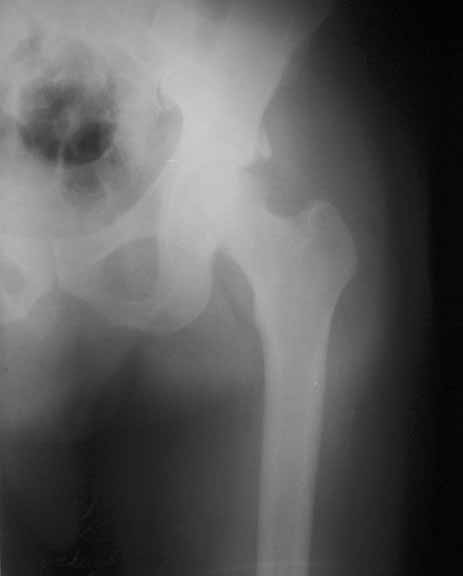

Middle aged adult hospital employee invoved in a road traffic accident. Suffered closed hip dislocation left side and fracture both bones right forearm(ulna compound) Underwent closed reduction of right hip and debridement with ORIF of forearm. Pre op X-ray showed acetabular rim fracture and post op X-ray showed a suspicious fracture line through the head of femur. One fragment of acetabulum seen displaced. CT done subsequently shows an undisplaced fracture through the head of femur with the acetabular rim fracture which is displaced.

1) Posterior aproach to fix the acetabular rim and fix the head fracture simultaneosly. To fix the fracture from the trochanter the problem will be the width of the proximal fragment (less than 1.45 cm in the maximum width - measured from CT monitor). This means that I cannot lag the fragment from the trochanter. In fact if I try for that the fragment could get displaced. Other option was to consider fixation from the head while fixing the posterior lip and countersink the screw head.

The femoral head fracture in Dr. George's (unknown age or medical conditions) male patient is essentially nondisplaced, the hip joint is congruent, there is no joint debris, and the wall is peripheral. Leave it alone.